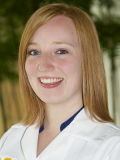

Microscopic (histologic) images

Contributed by Stephanie L. Skala, M.D. and Yuri Tachibana, M.D.

Chronic endometritis

Xanthogranulomatous endometritis